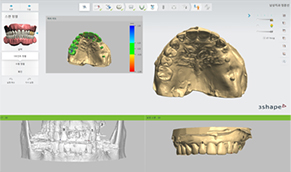

오스카55플란트치과는 무치악 환자의 틀니 스캔부터

플래닝, 가이드 제작, 시술, 최종 보철에 이르는

전 과정을 FULL DIGITAL 디지털화 하여 정밀함을 높였습니다.

OSCAR All-on-X 임플란트란?

오스카55플란트치과 OSCAR All-on-4 임플란트는

적은 식립으로 전체 임플란트가 가능합니다.

치아가 하나도 없는 경우에도 4개의

소수 임플란트를 식립하여 전체 치아를 수복합니다.